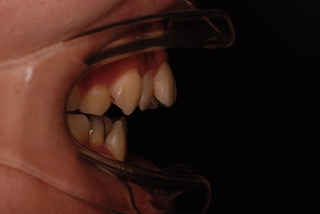

当院で行われた症例です。

下図の正面と横から見た前歯をご覧ください。

完全に前歯が開いてしまっていますね。

経過をご覧ください。